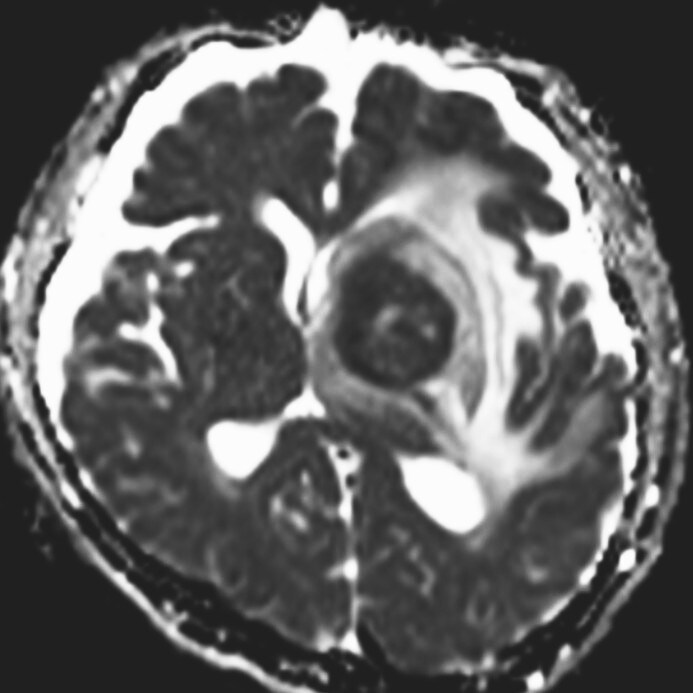

認知機能低下、行動異常、右不全片麻痺の進行を認め、頭蓋内の精査目的に頭部MRIが施行された。左大脳基底核に腫瘍性病変および腫瘍周囲浮腫の所見を認めた。同病変は、造影T1強調像画像では極めて淡い軽度の造影効果を示し、拡散強調画像では軽度の高信号、ADC画像では低信号を示した。診断確定のため生検手術を行った。生検手術1週間後に頭部MRIを施行すると、術前に施行した頭部MRIとは所見が変化し、左大脳基底核の病変は造影T1強調画像では明瞭な造影効果を認め、拡散強調画像でも高信号の増強、ADC画像では低信号を示した。病理組織学的診断は中枢神経系原発悪性リンパ腫であった。そのためR-MPV療法(リツキシマブ、メトトレキサート、プロカルバジン、ビンクリスチン)を施行した。R-MPV療法の経過中の頭部MRIでは、左大脳基底核の病変は縮小傾向を認め、それに伴い初診時に認めていた認知機能低下、行動異常、右不全片麻痺は改善傾向にあり、良好に経過している。